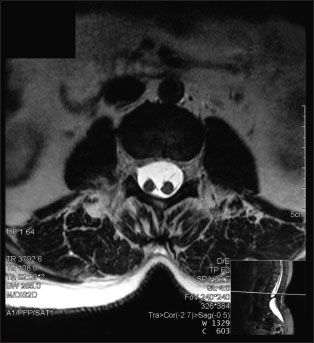

A 26-year-old woman at 30 weeks’ gestation presented to the emergency department with a throbbing frontal headache of 1 month’s duration. She had also had peripheral blurred vision for the past 2 weeks. Acetaminophen initially decreased her pain but was no longer effective. She had had a previous miscarriage.